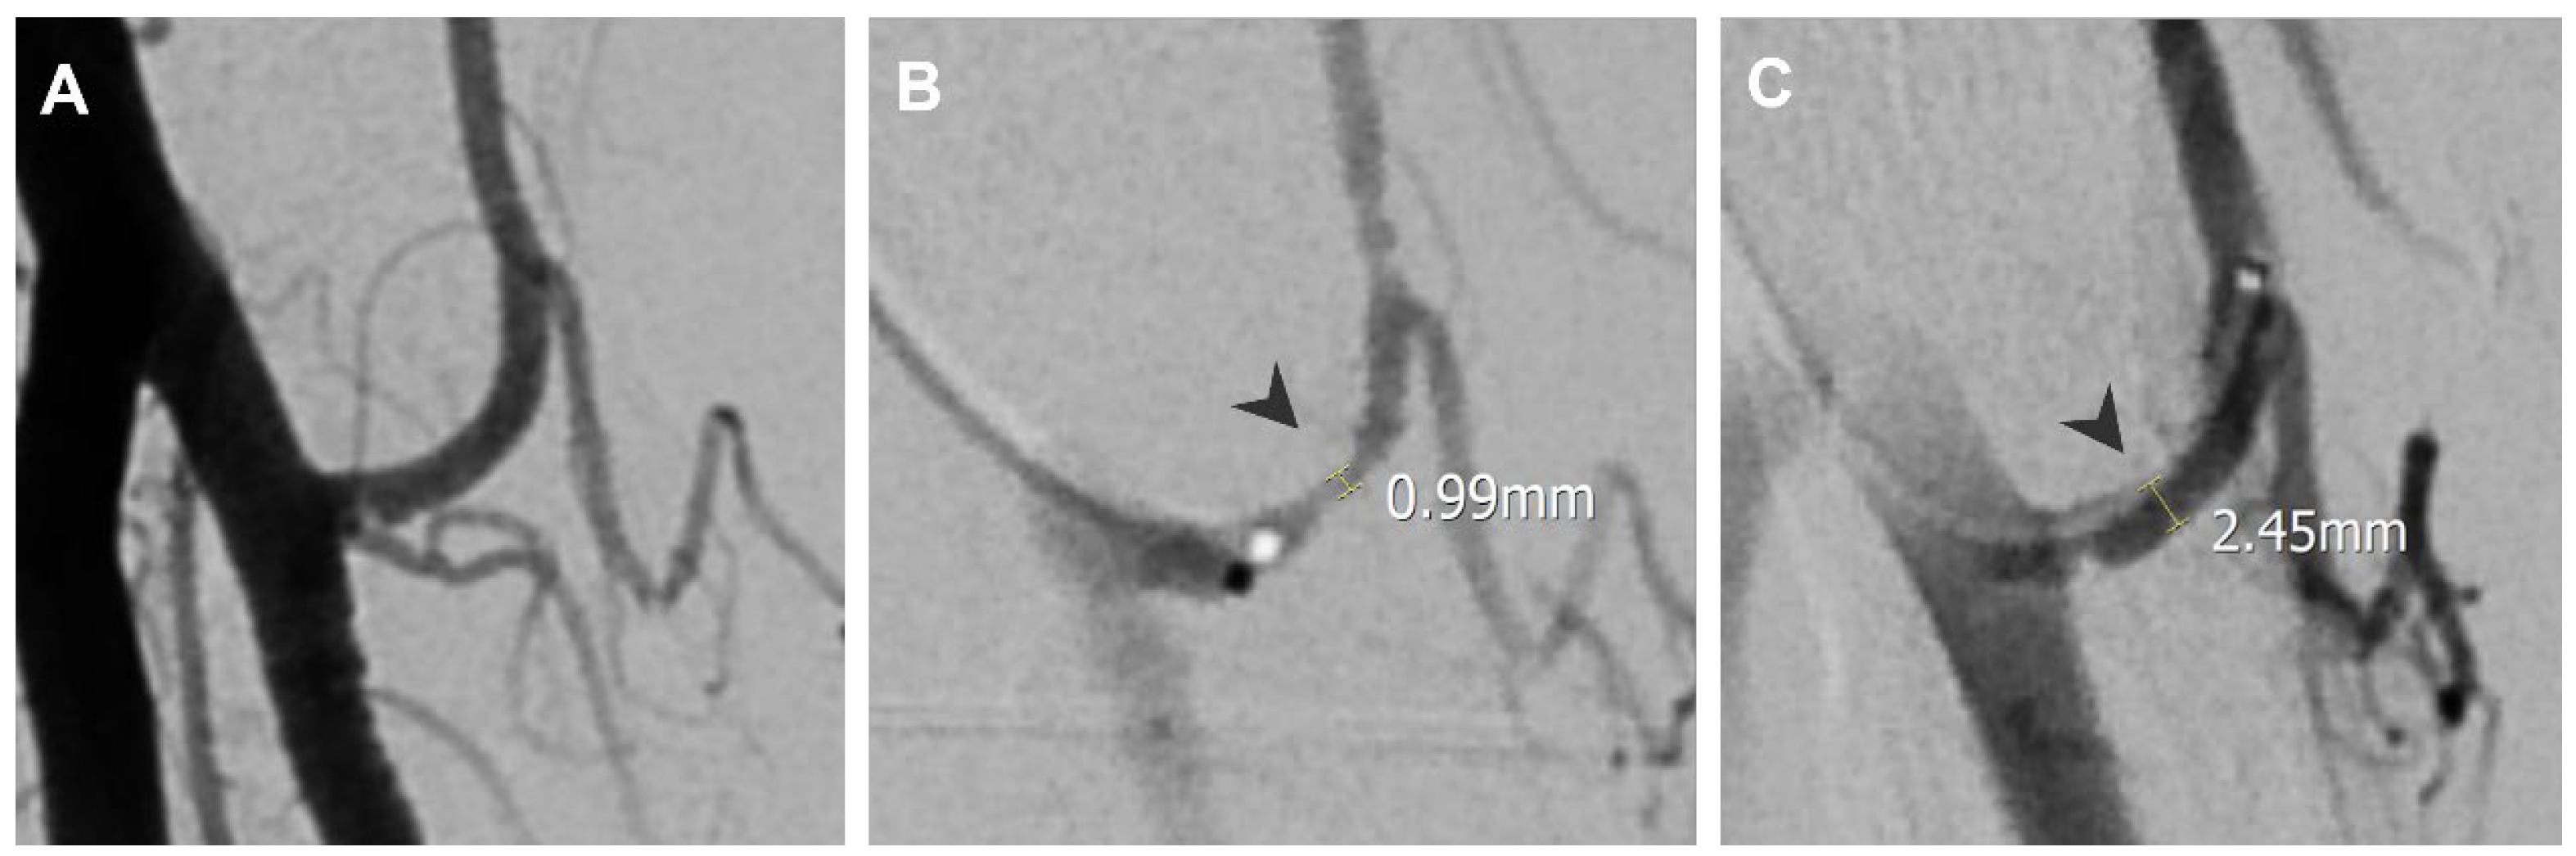

3.1. Lateral Epicondylitis

| Lateral epicondylitis | Radial recurrent artery | 1.00 | 2.5 |